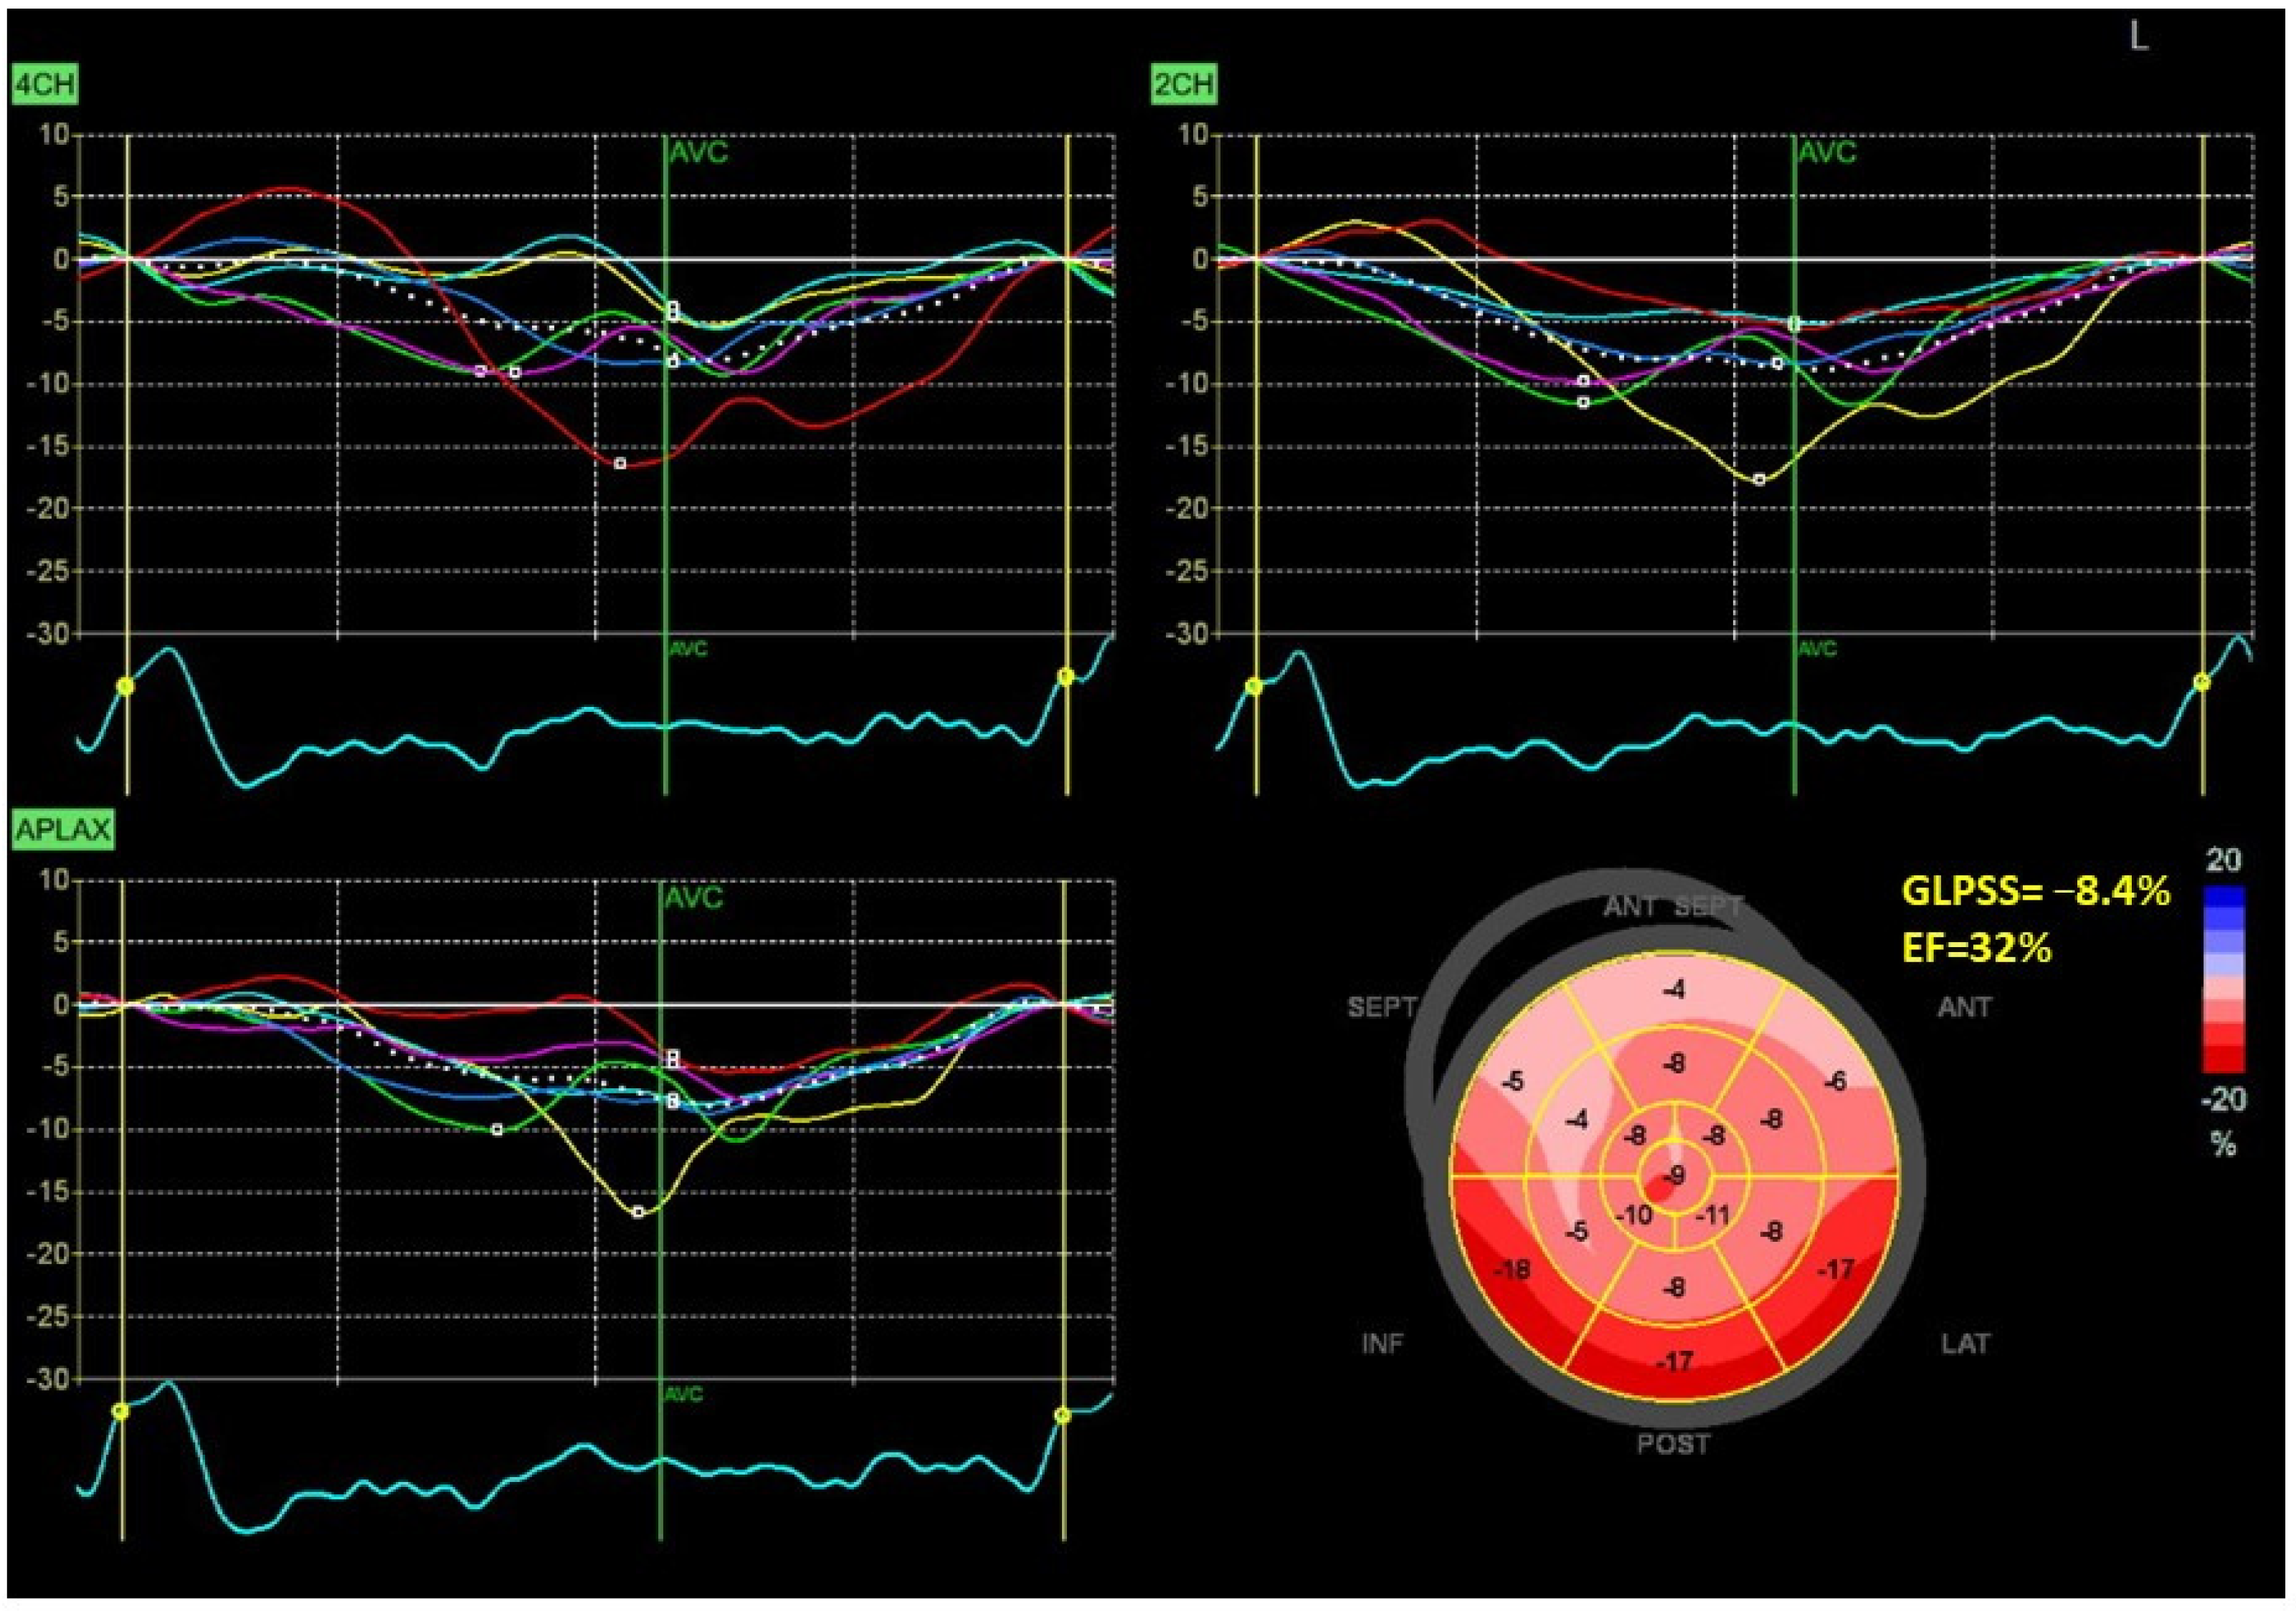

Figure 1 and Figure 2 show two contrasting examples (a healthy person and a patient after myocardial infarction and left bundle branch block) of STE curves with GLPSS, LVEF and LV pressure–strain loops and results of GWE for all LV segments.

Figure 2.

An example of echocardiography of a 61-year-old man with the left bundle branch block and a history of myocardial infarction. A set of individual longitudinal strain curves for all segments shown in different colors, with the average curve shown as a white dotted line, a bull’s eye of segmental longitudinal peak systolic strains and a summary of global longitudinal peak systolic strain (GLPSS) are shown in the top panel. The LV pressure–strain loop with the bull’s eye representation of myocardial work efficiency for each of the segments and a summary of all myocardial work indices are shown in the lower panel. Abbreviations: GLS—global longitudinal peak systolic strain, EF—ejection fraction, GWI—global myocardial work index, GCW—global constructive work, GWW—global wasted work, GWE—global work efficiency, BP—blood pressure.